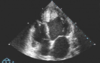

25-årig kvinde med en nydiagnosticeret hæmatologisk lidelse kommer til rutineundersøgelse i hjertemedicinsk ambulatorium. Hun har ingen kardiovaskulære symptomer. Patientens ekkokardiografi er vist i nedenfor.

Hvilket af følgende tiltag er mest korrekt?

- a) Behandling med Acetylsalicylsyre og Clopidogrel.

- b) Behandling med lavmolekylært Heparin og Marevan.

- c) Behandling med Alteplase (blodprop opløsende) og ufraktioneret Heparin.

- d) Akut koronararteriografi.

- e) Kirurgisk intervention.

b) Behandling med lavmolekylært Heparin og Marevan.